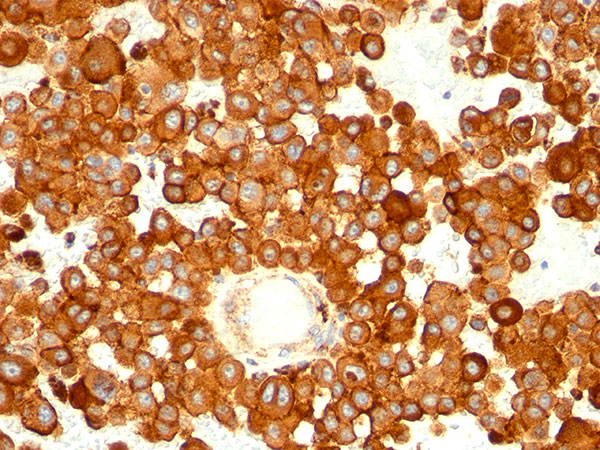

Formalin-paraffin human melanoma stained with CD63 MAb (MX-49.129.5) |